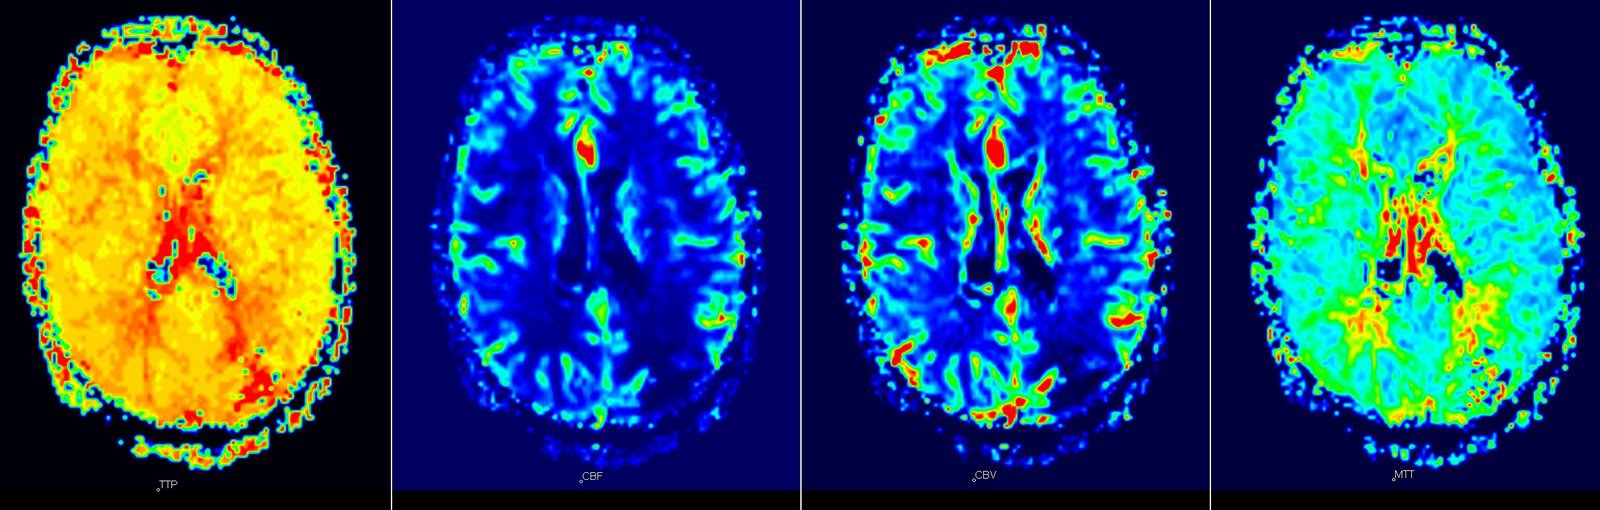

Chụp cộng hưởng từ tưới máu là gì?

- Chụp cộng hưởng từ tưới máu (MRI perfusion) nhằm đánh giá vi tuần hoàn não giúp xác định khả năng sống còn của nhu mô não vùng bị tổn thương.

- Chụp tưới máu não: tiêm bolus thuốc đối quang từ (gadolinium) với liều 0.2ml/kg cân nặng với tốc độ 5ml/s sau đó đuổi thuốc bằng nước muối sinh lý 20ml với cùng tốc độ tiêm. Chụp ngay sau khi bắt đầu bơm thuốc với chuỗi xung T2*, trường khảo sát gồm toàn bộ nhu mô não, lặp lại liên tục trong 40-45 giây.

- Tính toán các thông số tưới máu: Thời gian đến bolus, thời gian đạt đỉnh (TTP), thời gian đi qua trung bình biểu kiến (MTT), Thể tích máu não tương đối (CBV), đỉnh cao nhất (MAX), chỉ số lưu thông máu não (CBFI).

- Dựa trên hình ảnh và các thông số của chụp cộng hưởng từ tưới máu, bác sĩ sẽ đánh giá được tổn thương nhu mô não (nếu có), mức độ khuếch tán nhu mô não và khả năng hồi phục của nhu mô não tổn thương, từ đó tư vấn chuyên môn cho người bệnh và người nhà bệnh nhân nếu có yêu cầu.